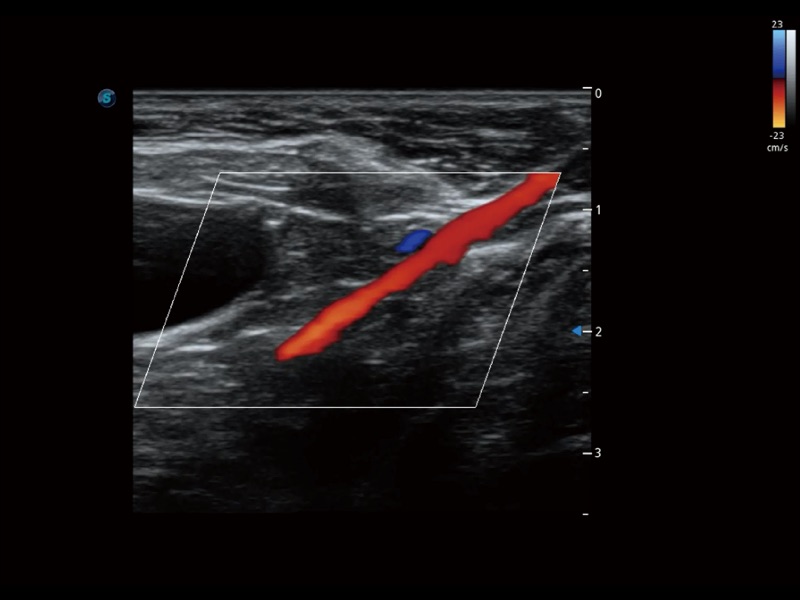

通過(guò)色彩血流和實(shí)時(shí)寬景相結(jié)合,可觀察到完整的靜脈或動(dòng)脈的血流,方便醫(yī)生檢查。實(shí)時(shí)掃查過(guò)程中,如有任何操作失誤也可以很容易地進(jìn)行回掃擦除,而不會(huì)中斷掃查。